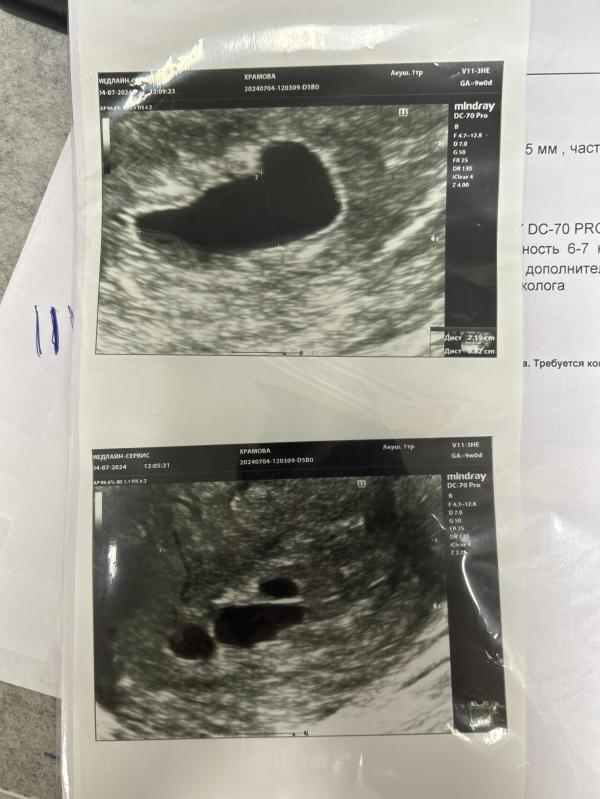

4.07.2024 иду на УЗИ- эмбриона так и нет, акушерская неделя 9 недель, по размеру плодного яйца-6-7, т.е. с момента прошлого УЗИ прошло 2 недели…

Гематома рассосалась, но на плодном яйце обнаружились 3 мини-плодных яйца… Как на картошке «детки».

@irina_01-23 вижу, почему-то не сразу фото увидела. К сожалению, скорее всего анэмбриония( По идее до 25мм ещё может появиться эмбрион, но рост 3мм за 2 недели и расщепление плодного яйца ничего хорошего не сулят. Мне очень жаль

Похоже что да 😔 Какой размер плодного яйца?